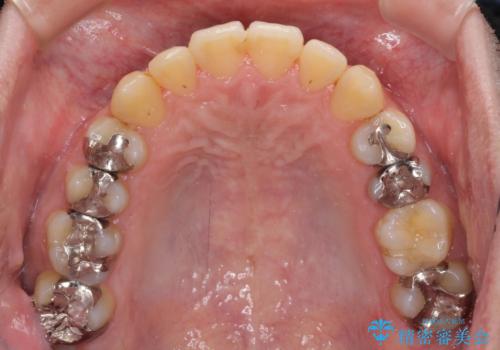

前歯のクロスバイトをインビザラインで矯正治療

- 前歯のデコボコとクロスバイトを気にして来院された患者様です。

前歯を早く整えたいとの希望があったので、ワイヤー矯正にて短期間でクロスバイトを解消し、その後インビザラインにて整えることとしました。

インビザラインによる前歯のクロスバイト改善におけるリスクとして、前歯歯髄充血・歯髄壊死が挙げられます。

ワイヤー矯正を併用する目的として、短期間でデコボコやクロスバイトを改善する他に、歯髄充血リスクを低減させるというものがあります。